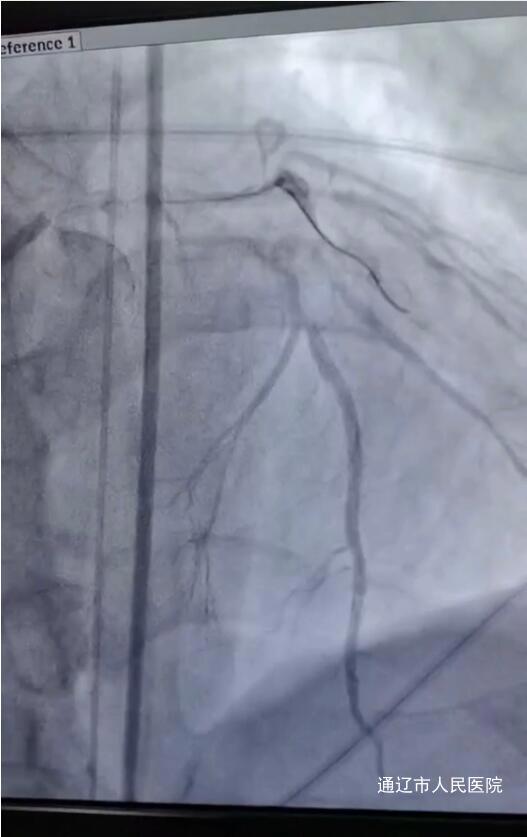

时间就是生命,我院立即对患者开通绿色通道,紧急行冠脉造影术,初期家属拒绝支架,返回CCU继续治疗,在李军主任及主治医生包瑞娜反复沟通下家属同意开通血管。心血管内三科郑崔成主任团队迅速行动,为患者行冠脉造影术及支架术,并行球囊扩张术,CCU配合心内三团队快速完成中心静脉置管,辅助放置IABP,术后进入CCU进一步治疗。